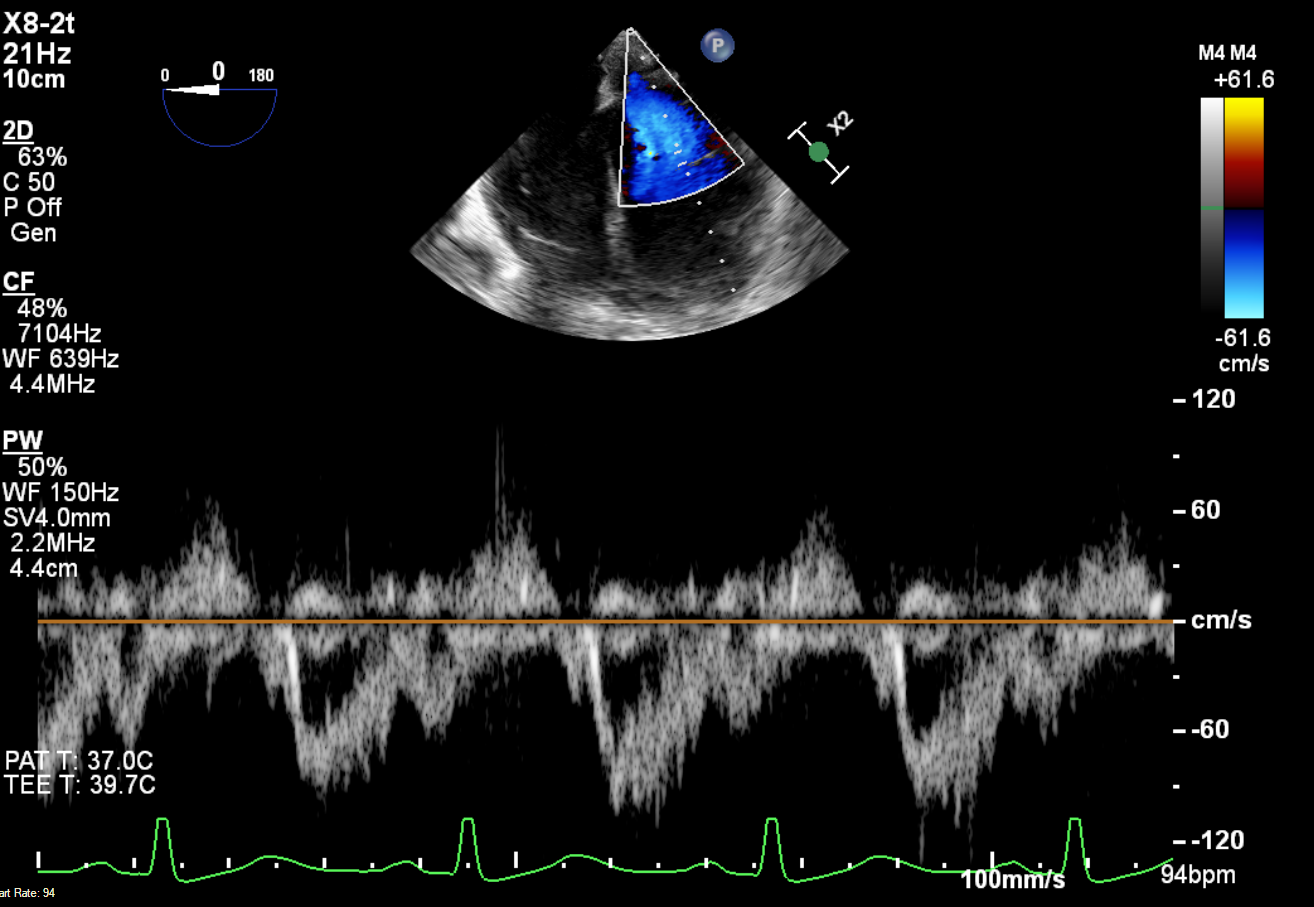

Suprasternal image is shown below. Combined colour Doppler and M mode of flow in the descending aorta is shown. Findings are consistent with